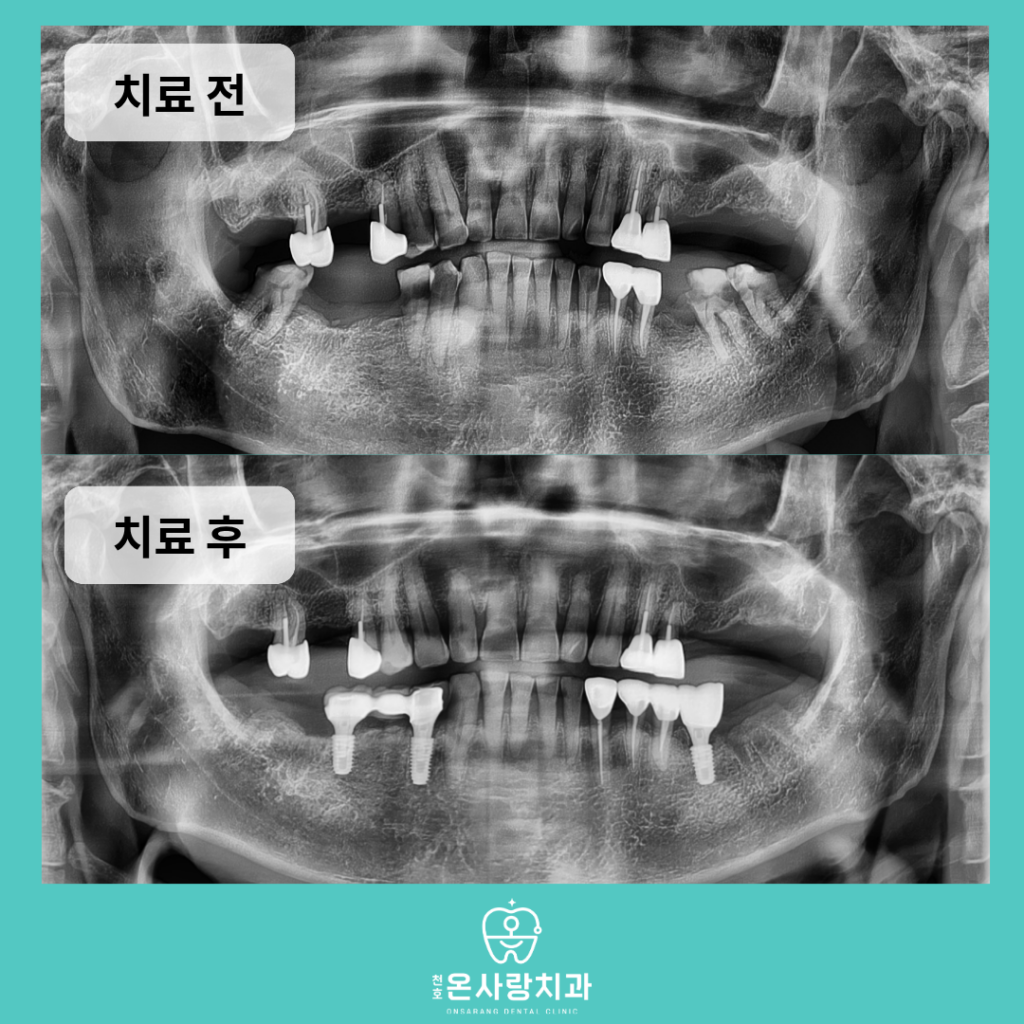

최종적으로 하악 구치부 치료가 완료된 후

환자분께서는 그동안 겪어왔던

통증에서 벗어나 한결 편안해진 모습을 보여주셨습니다.

가장 뒤쪽 어금니를 제외하였음에도 불구하고

첫 번째 큰어금니를 통해 안정적인

식사가 가능해졌으며 상악의 틀니와도

조화로운 맞물림을 이루게 되었습니다.

환자분께서는 본인의 상황에 맞춘

합리적인 치료 계획 덕분에 심리적인 부담을 덜고

치료를 끝마칠 수 있었다며 매우 흡족해 하셨습니다.